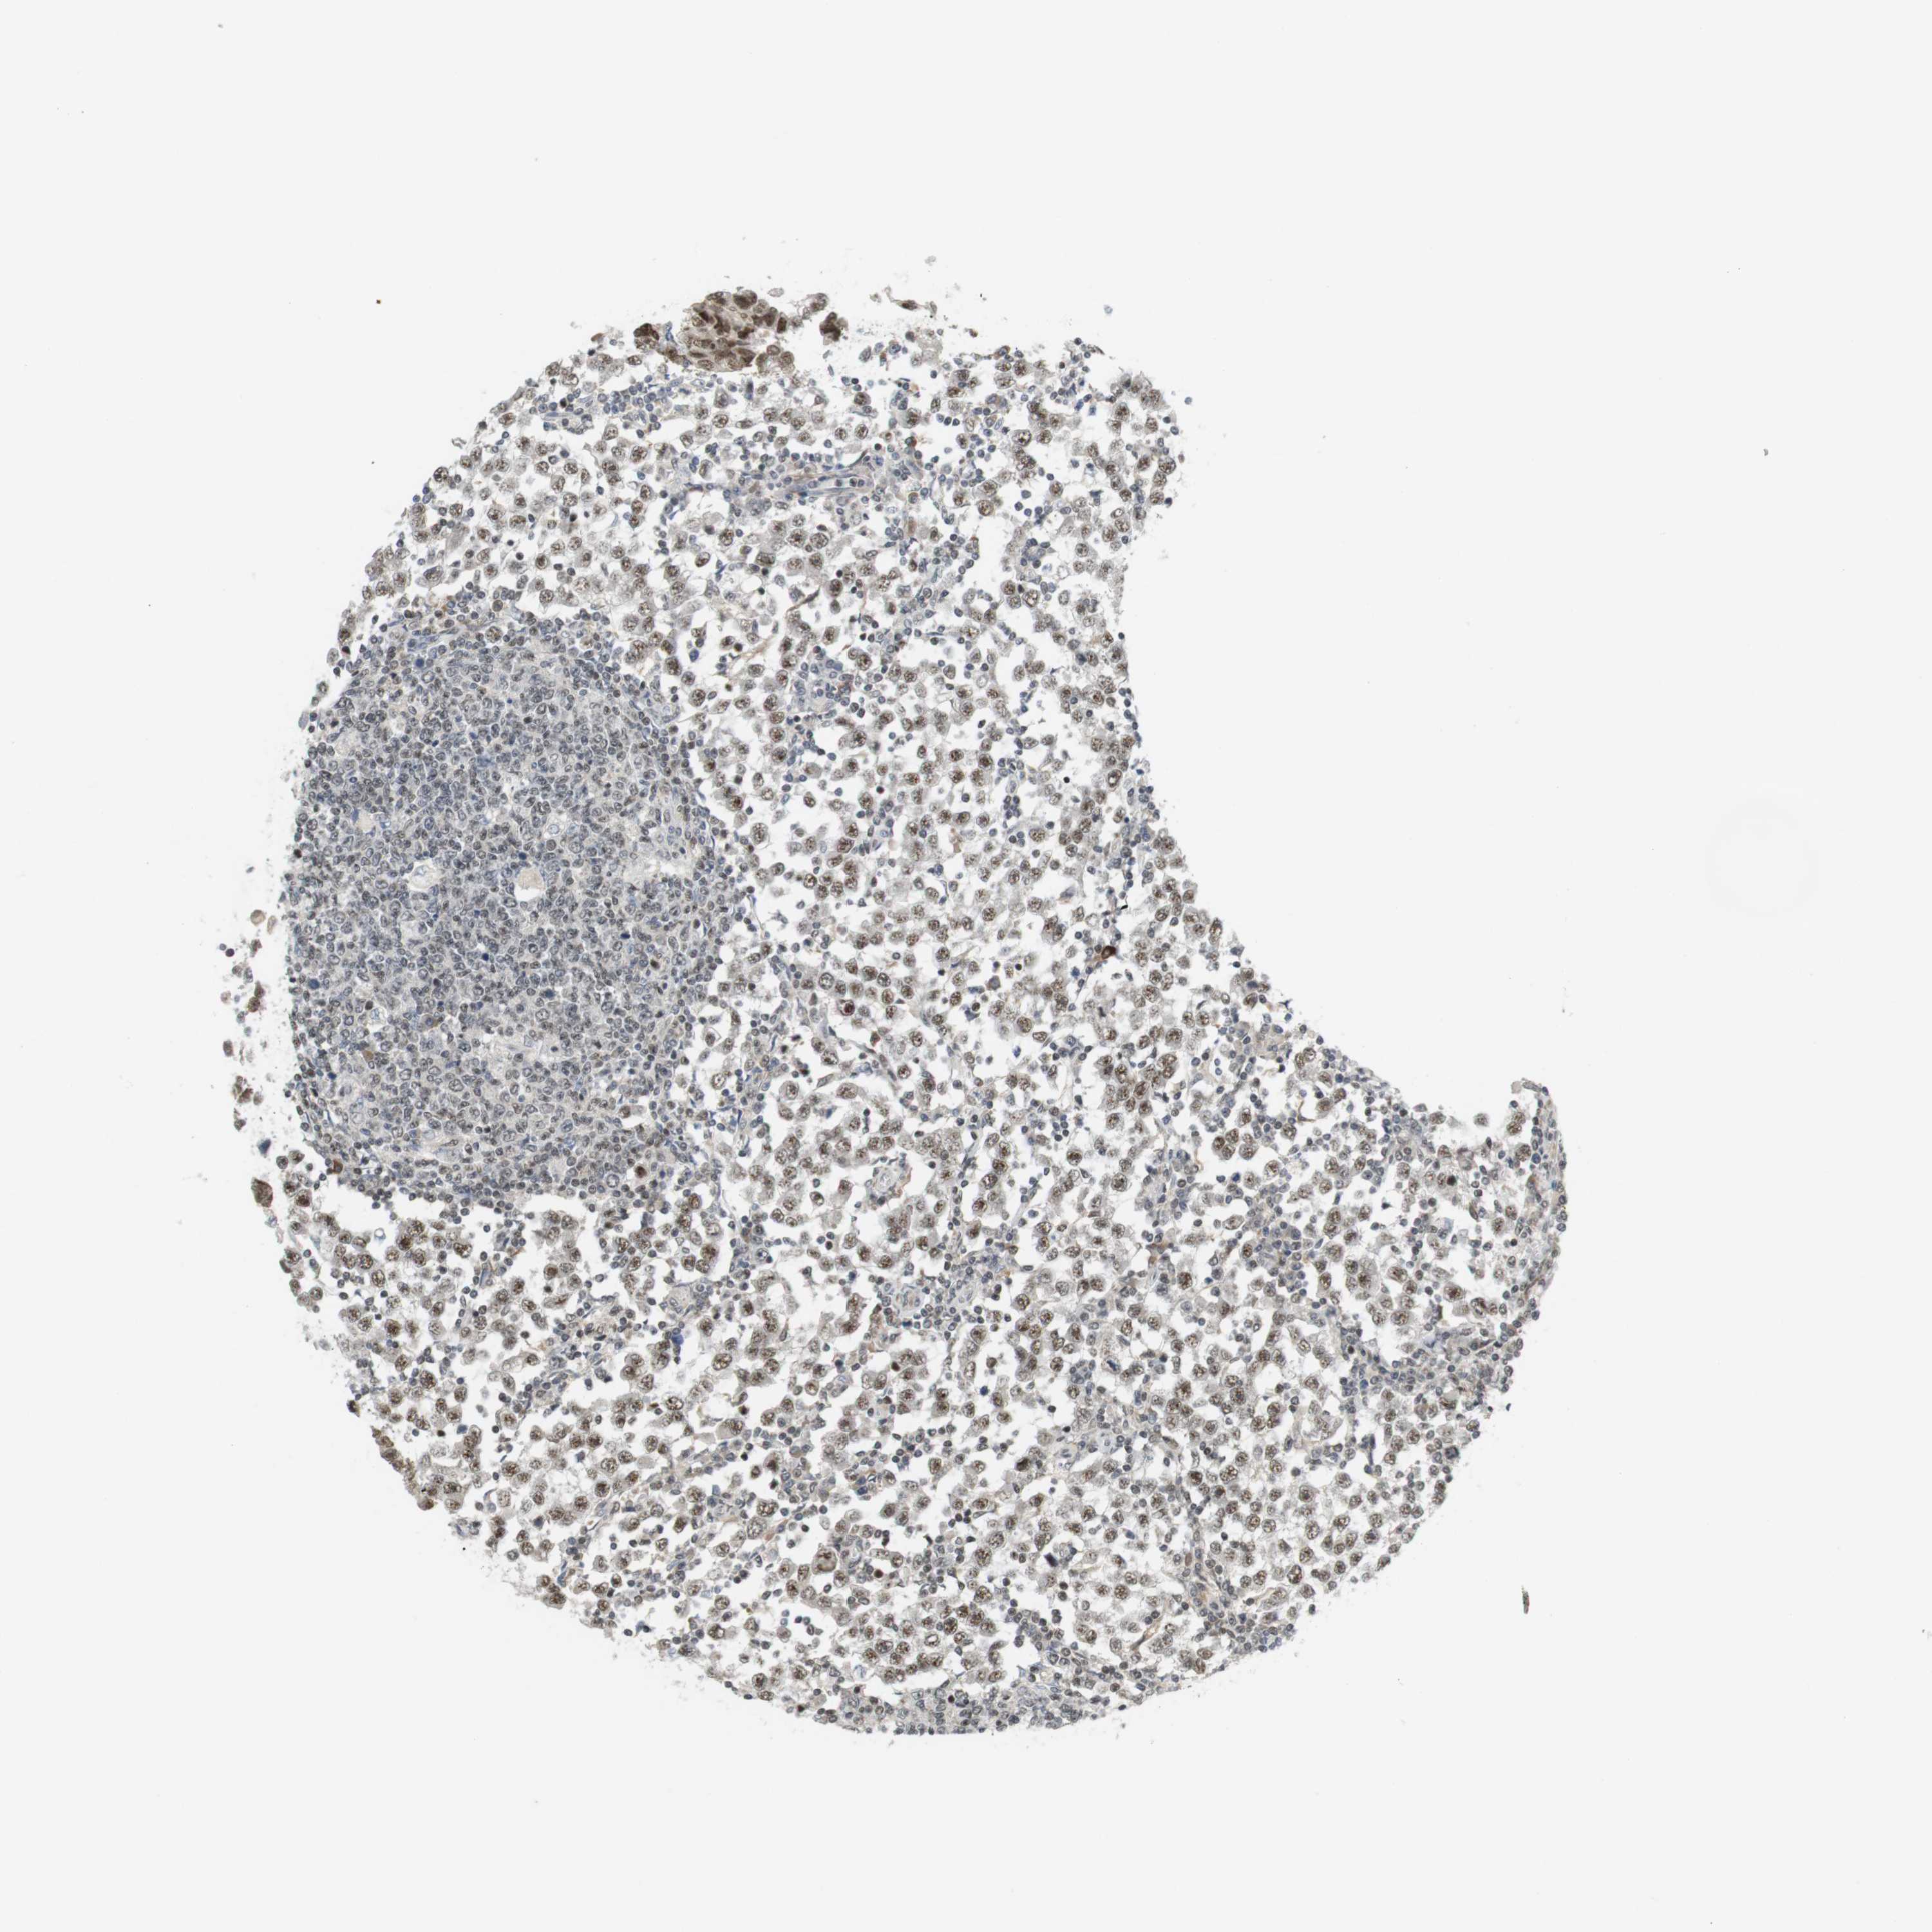

TESTIS CANCER - Protein expressioni

A mouse-over function shows sample information and annotation data. Click on an image to view it in a full screen mode. Samples can be filtered based on level of antibody staining by selecting one or several of the following categories: high, medium, low and not detected. The assay and annotation is described here.

Note that samples used for immunohistochemistry by the Human Protein Atlas do not correspond to samples in the TCGA dataset.

Antibody stainingi

Antibody staining in the annotated cell types in the current human tissue is reported as not detected, low, medium, or high, based on conventional immunohistochemistry profiling in selected tissues. This score is based on the combination of the staining intensity and fraction of stained cells.

Each image is clickable and will lead to virtual microscopy that enables deeper exploration of all samples and also displays staining intensity scores, fraction scores and subcellular localization as well as patient and tissue information for each sample.

Antibody HPA061646

Carcinoma, Embryonal, NOS

Seminoma, NOS